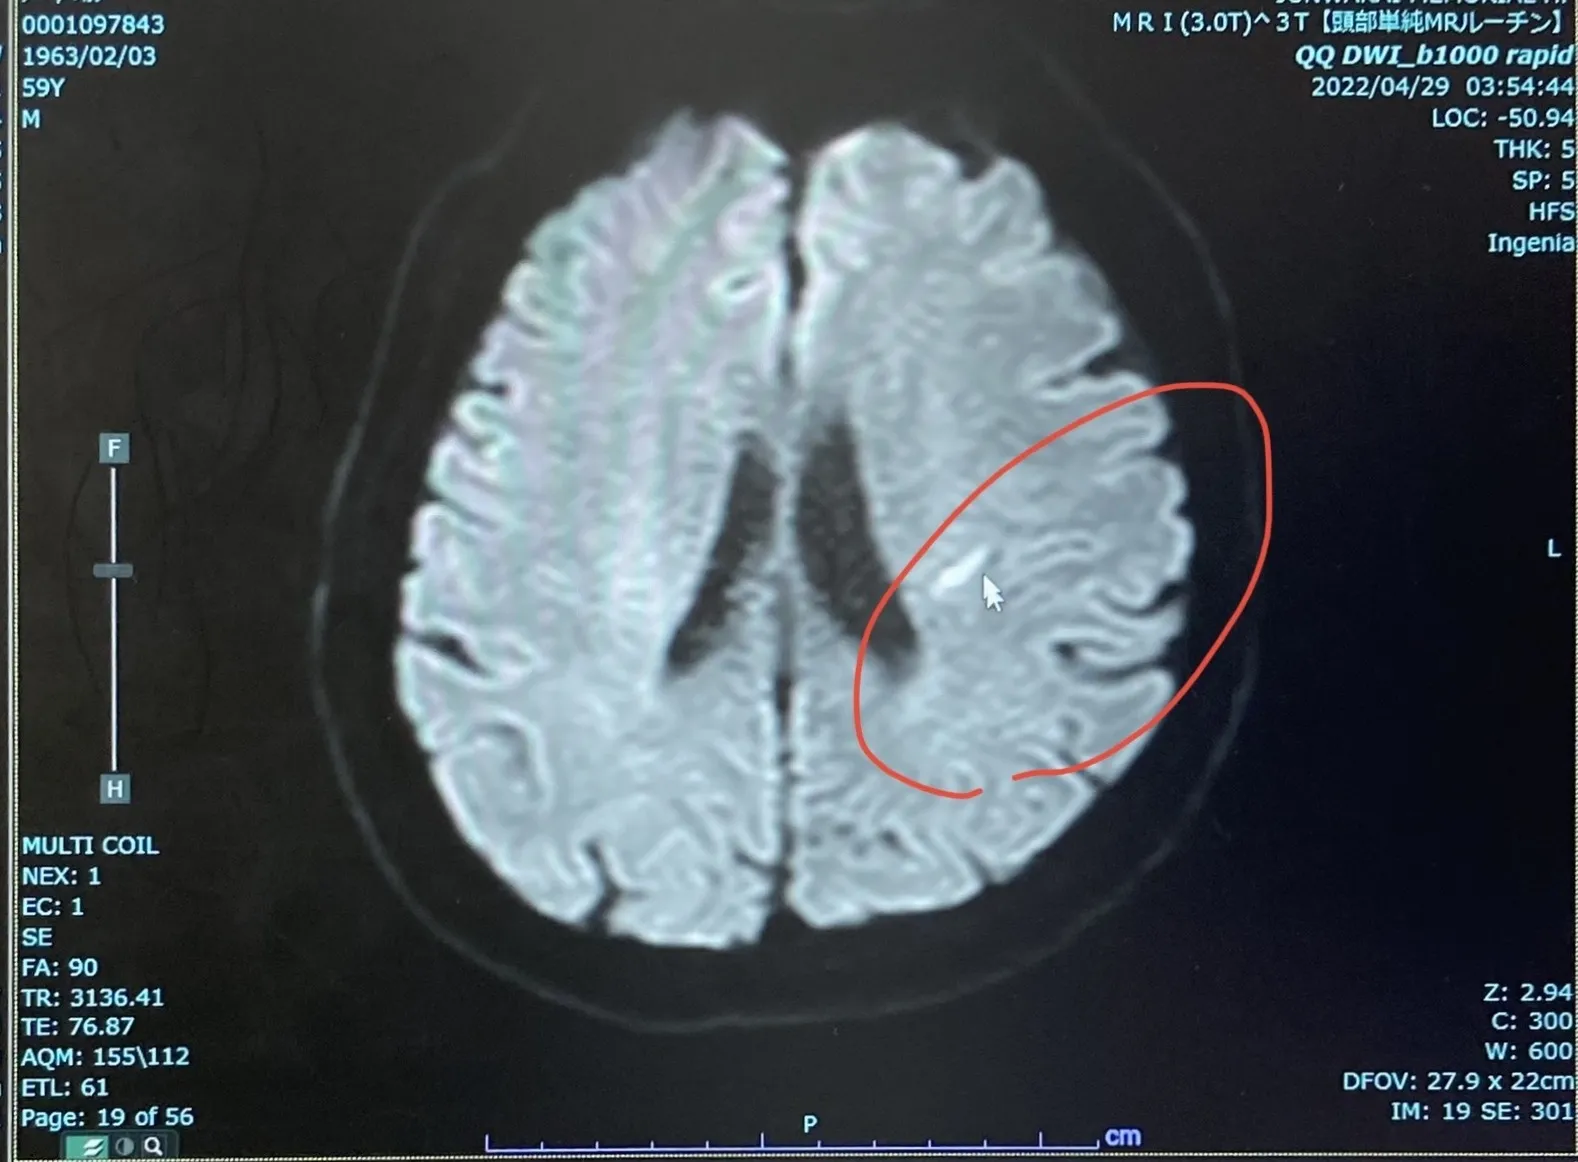

脳梗塞で入院でしたのに2週間後には走れました。